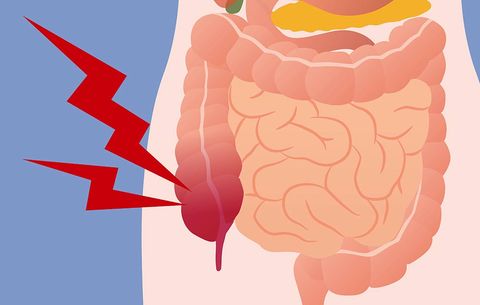

Artikel Kesehatan Mitra Keluarga Radang Usus Buntu

Artikel Kesehatan Mitra Keluarga Radang Usus Buntu